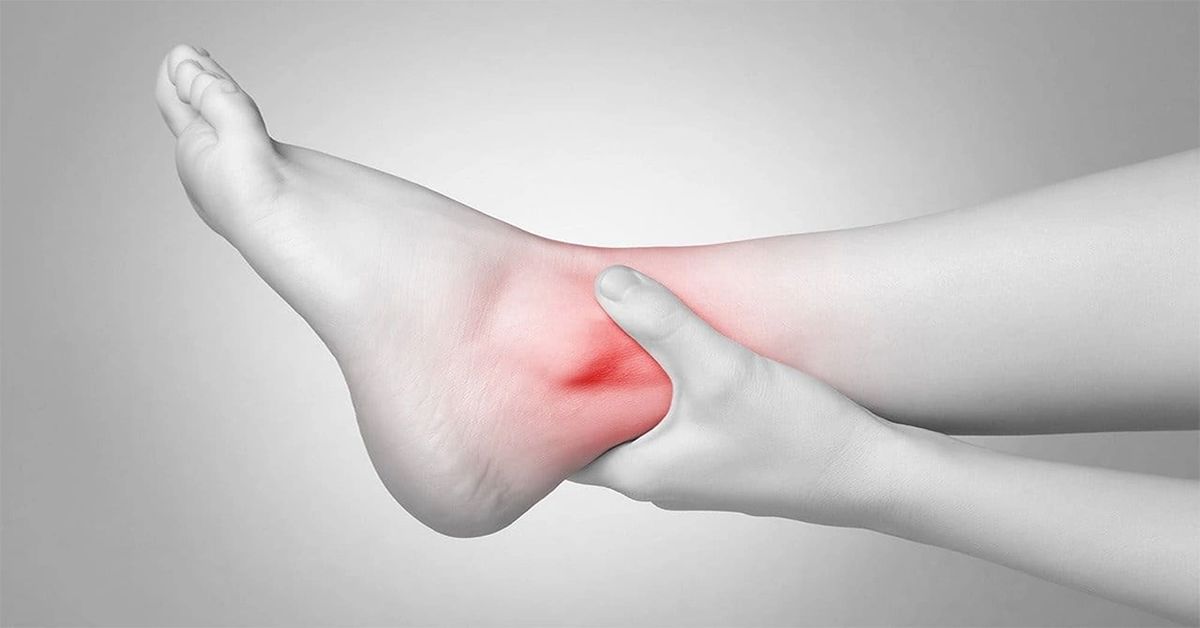

En yaygın belirtisi ayakta hissedilen ağrıdır. Ağrı genellikle ayak bileğinin iç tarafında veya orta bölümünde yoğunlaşır. Uzun süre ayakta kalmak, yürümek veya koşmak ağrıyı artırabilir. Bazı hastalar, dinlenme sonrasında ayağa kalktıklarında daha fazla ağrı hissedebilir. Ağrı, spor yaparken veya yoğun fiziksel aktiviteler sırasında daha belirgin hale gelir.

Bu kaynaşma problemi التحالف الرصغي olarak adlandırılır. Topuk veya ayak bileği çevresinde ağrı oluşur. Yorgunluk ve tekrarlayan burkulmalar şikâyetleri artırır. Tanı, fizik muayene ve radyolojik görüntülemelerle konur.

Ayak, vücudun dengesi ve hareketi için hayati bir yapıdır. Bazı kişilerde ayak kemiklerinden ikisi veya daha fazlası kaynaşmıştır. Bu durum, ayak hareketlerini kısıtlar ve zamanla ağrıya yol açabilir. Yürüyüş sırasında topuk veya bilek çevresinde rahatsızlık hissedilebilir. Özellikle çocukluk ve ergenlik döneminde fark edilebilir.